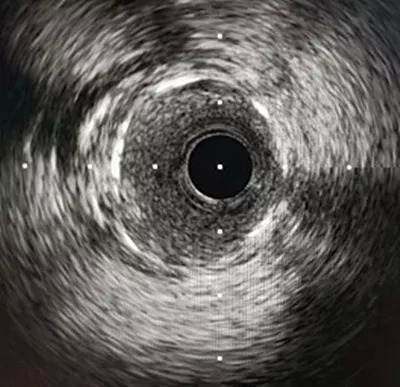

IVUS:远段支架扩张充分、贴壁良好